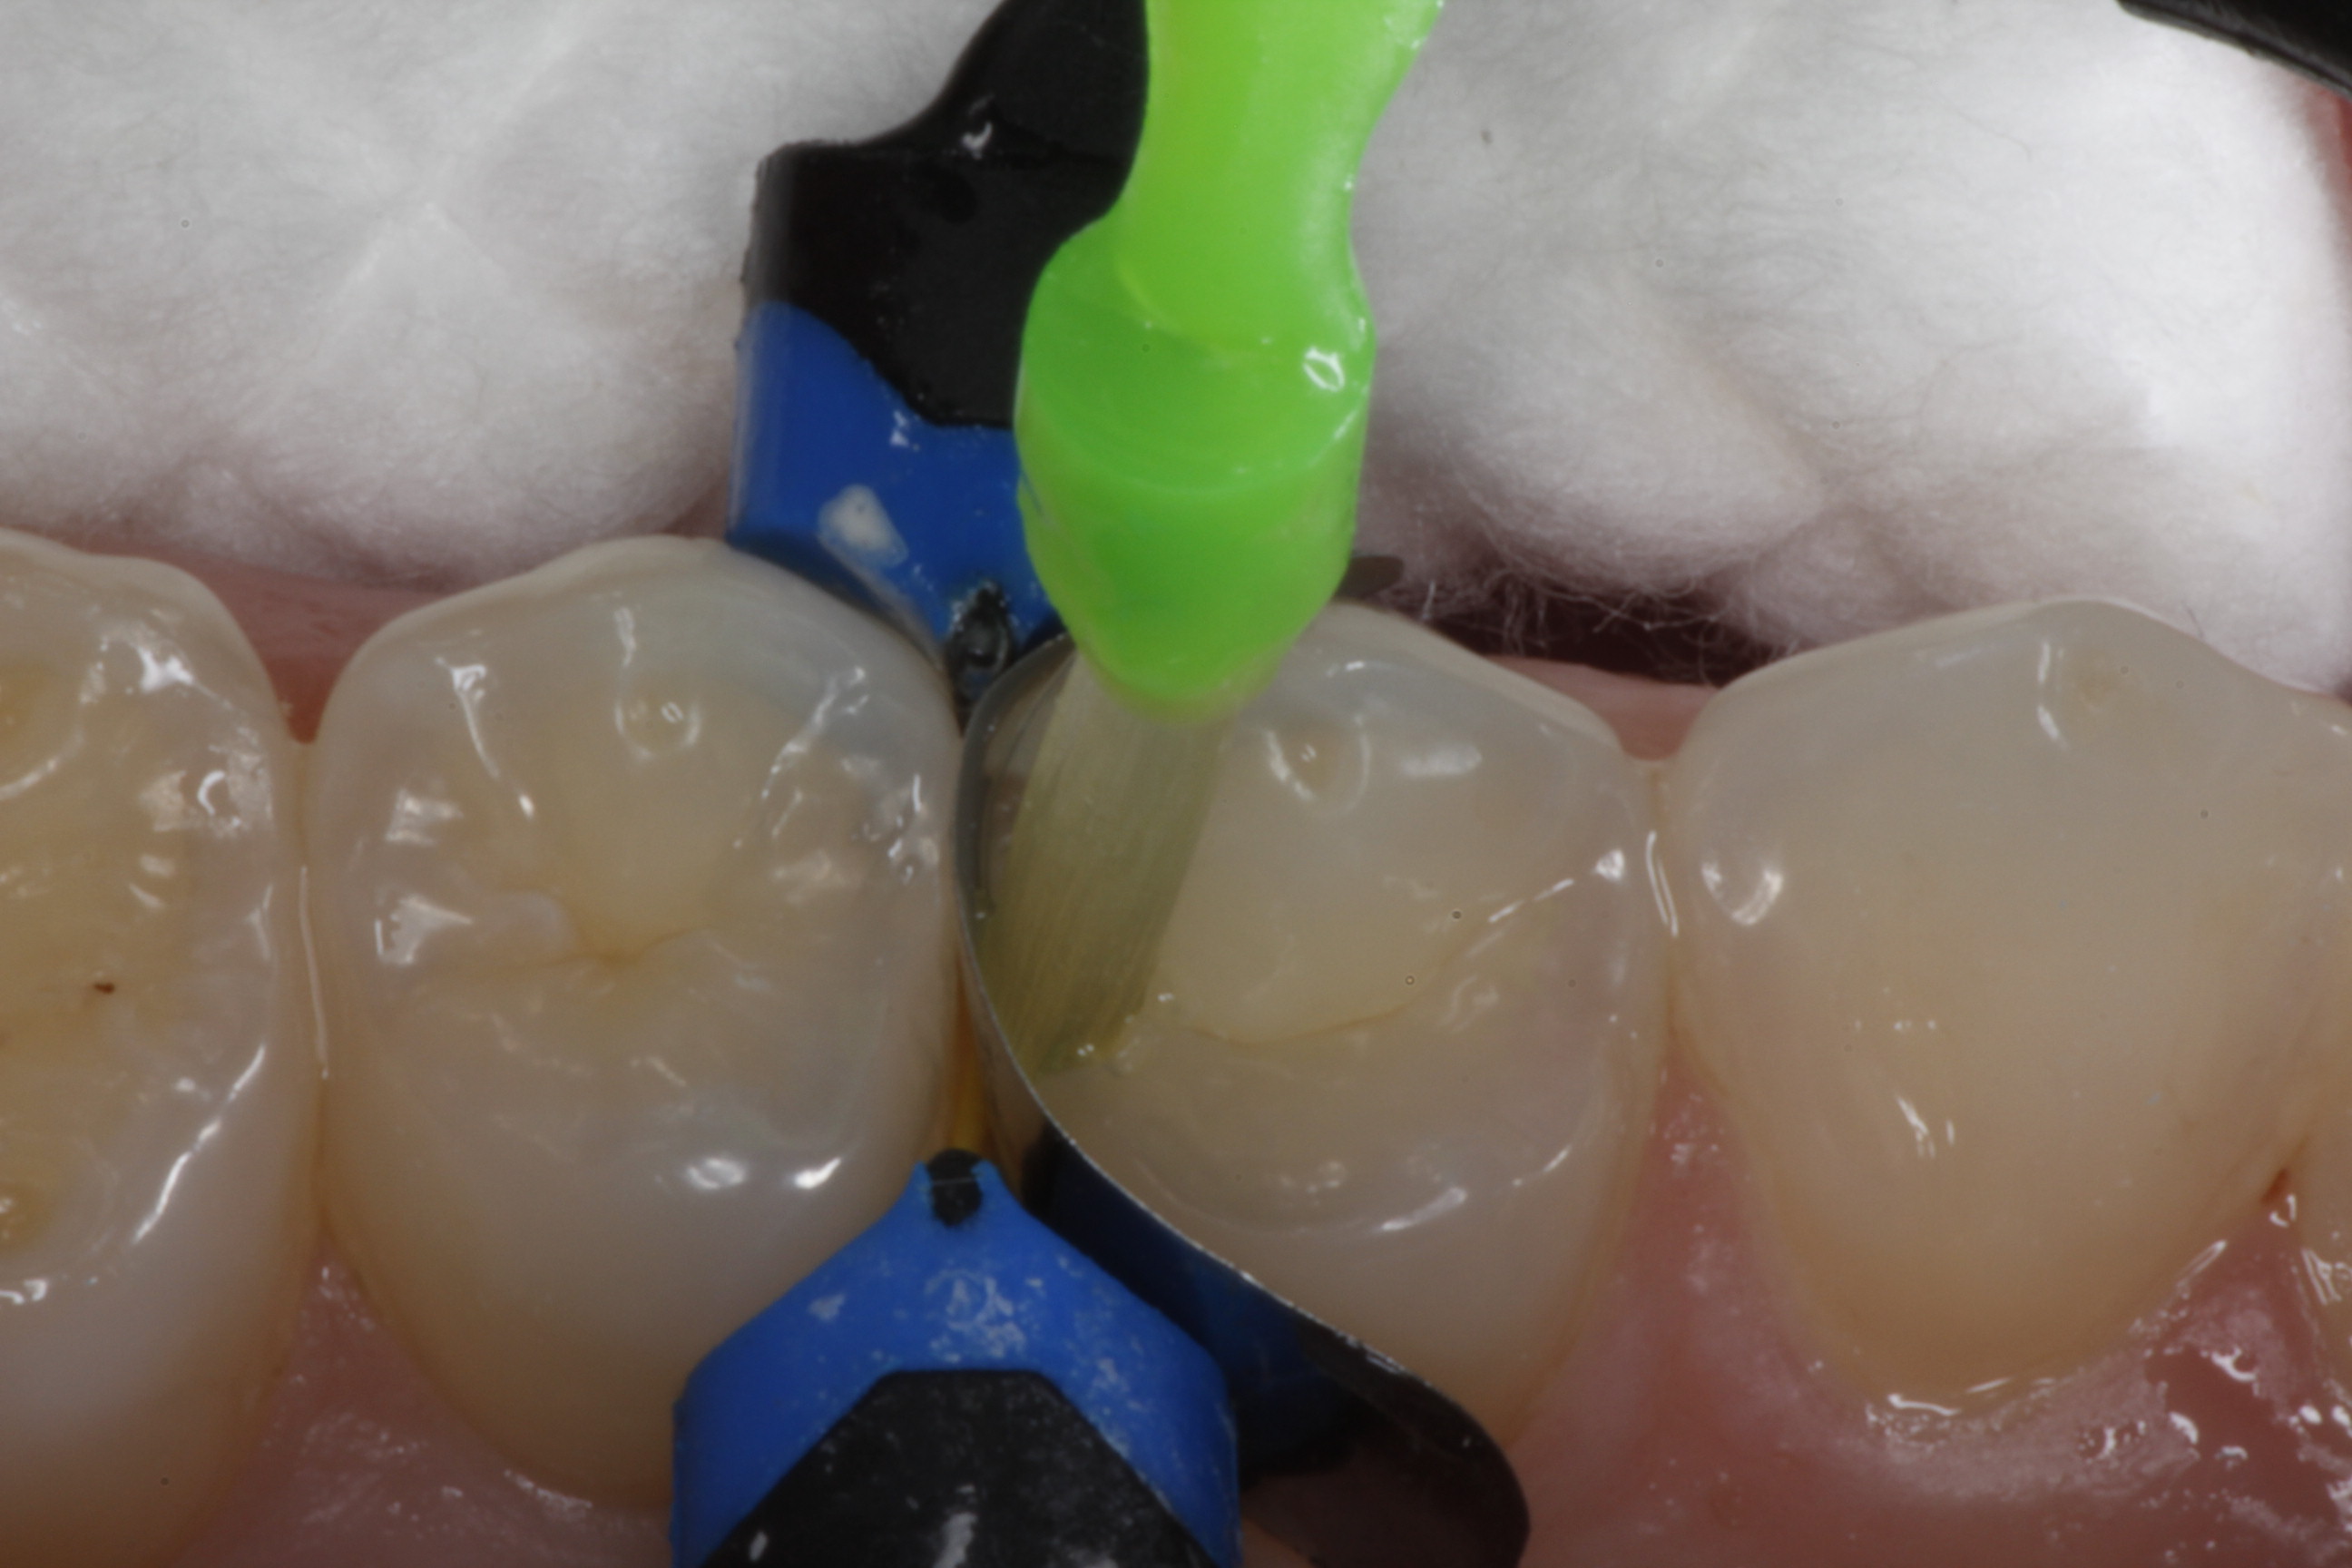

Fig 8. After isolation, a sectional matrix is placed to restore contact and proximal anatomic form to the composite to be placed. The goal is to perform as little rotary finishing and polishing as possible by having the matrix fit precisely to the cavity margins.

Figure 8

Fig 10. A Giomer bulk-fill flowable is used for this conservative slot preparation so that the entire cavity can be filled with one increment even though the depth of the proximal box is approximately 4 mm.

Figure 10